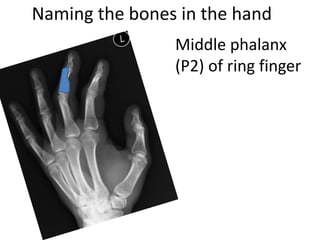

This document provides an overview of hand anatomy including:

- Naming the bones, joints, tendons, nerves and skin landmarks of the hand and wrist.